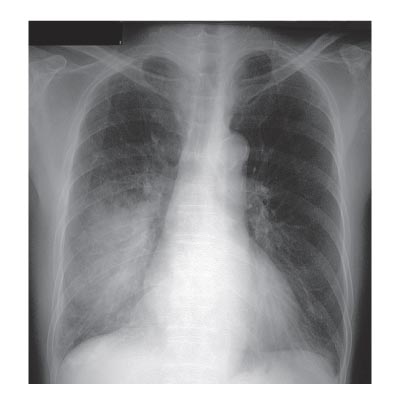

‘Community-acquired pneumonia’ (CAP) is een frequente oorzaak van ziekenhuisopnamen (figuur). De opnameduur hangt samen met efficiëntie en kosten, maar ook met complicaties, zoals nosocomiale infecties en diepveneuze trombose. Fishbane et al. onderzochten of de opnameduur bij CAP verkort kan worden door de toepassing van richtlijnen in combinatie met…